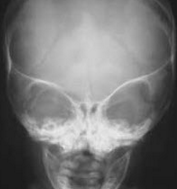

Cleidocranial Dysostosis

Douglas P. Beall, MD; John Whyte, MD, MPH

These findings are consistent with the midline fusion anomalies typically seen in cleidocranial dysostosis.